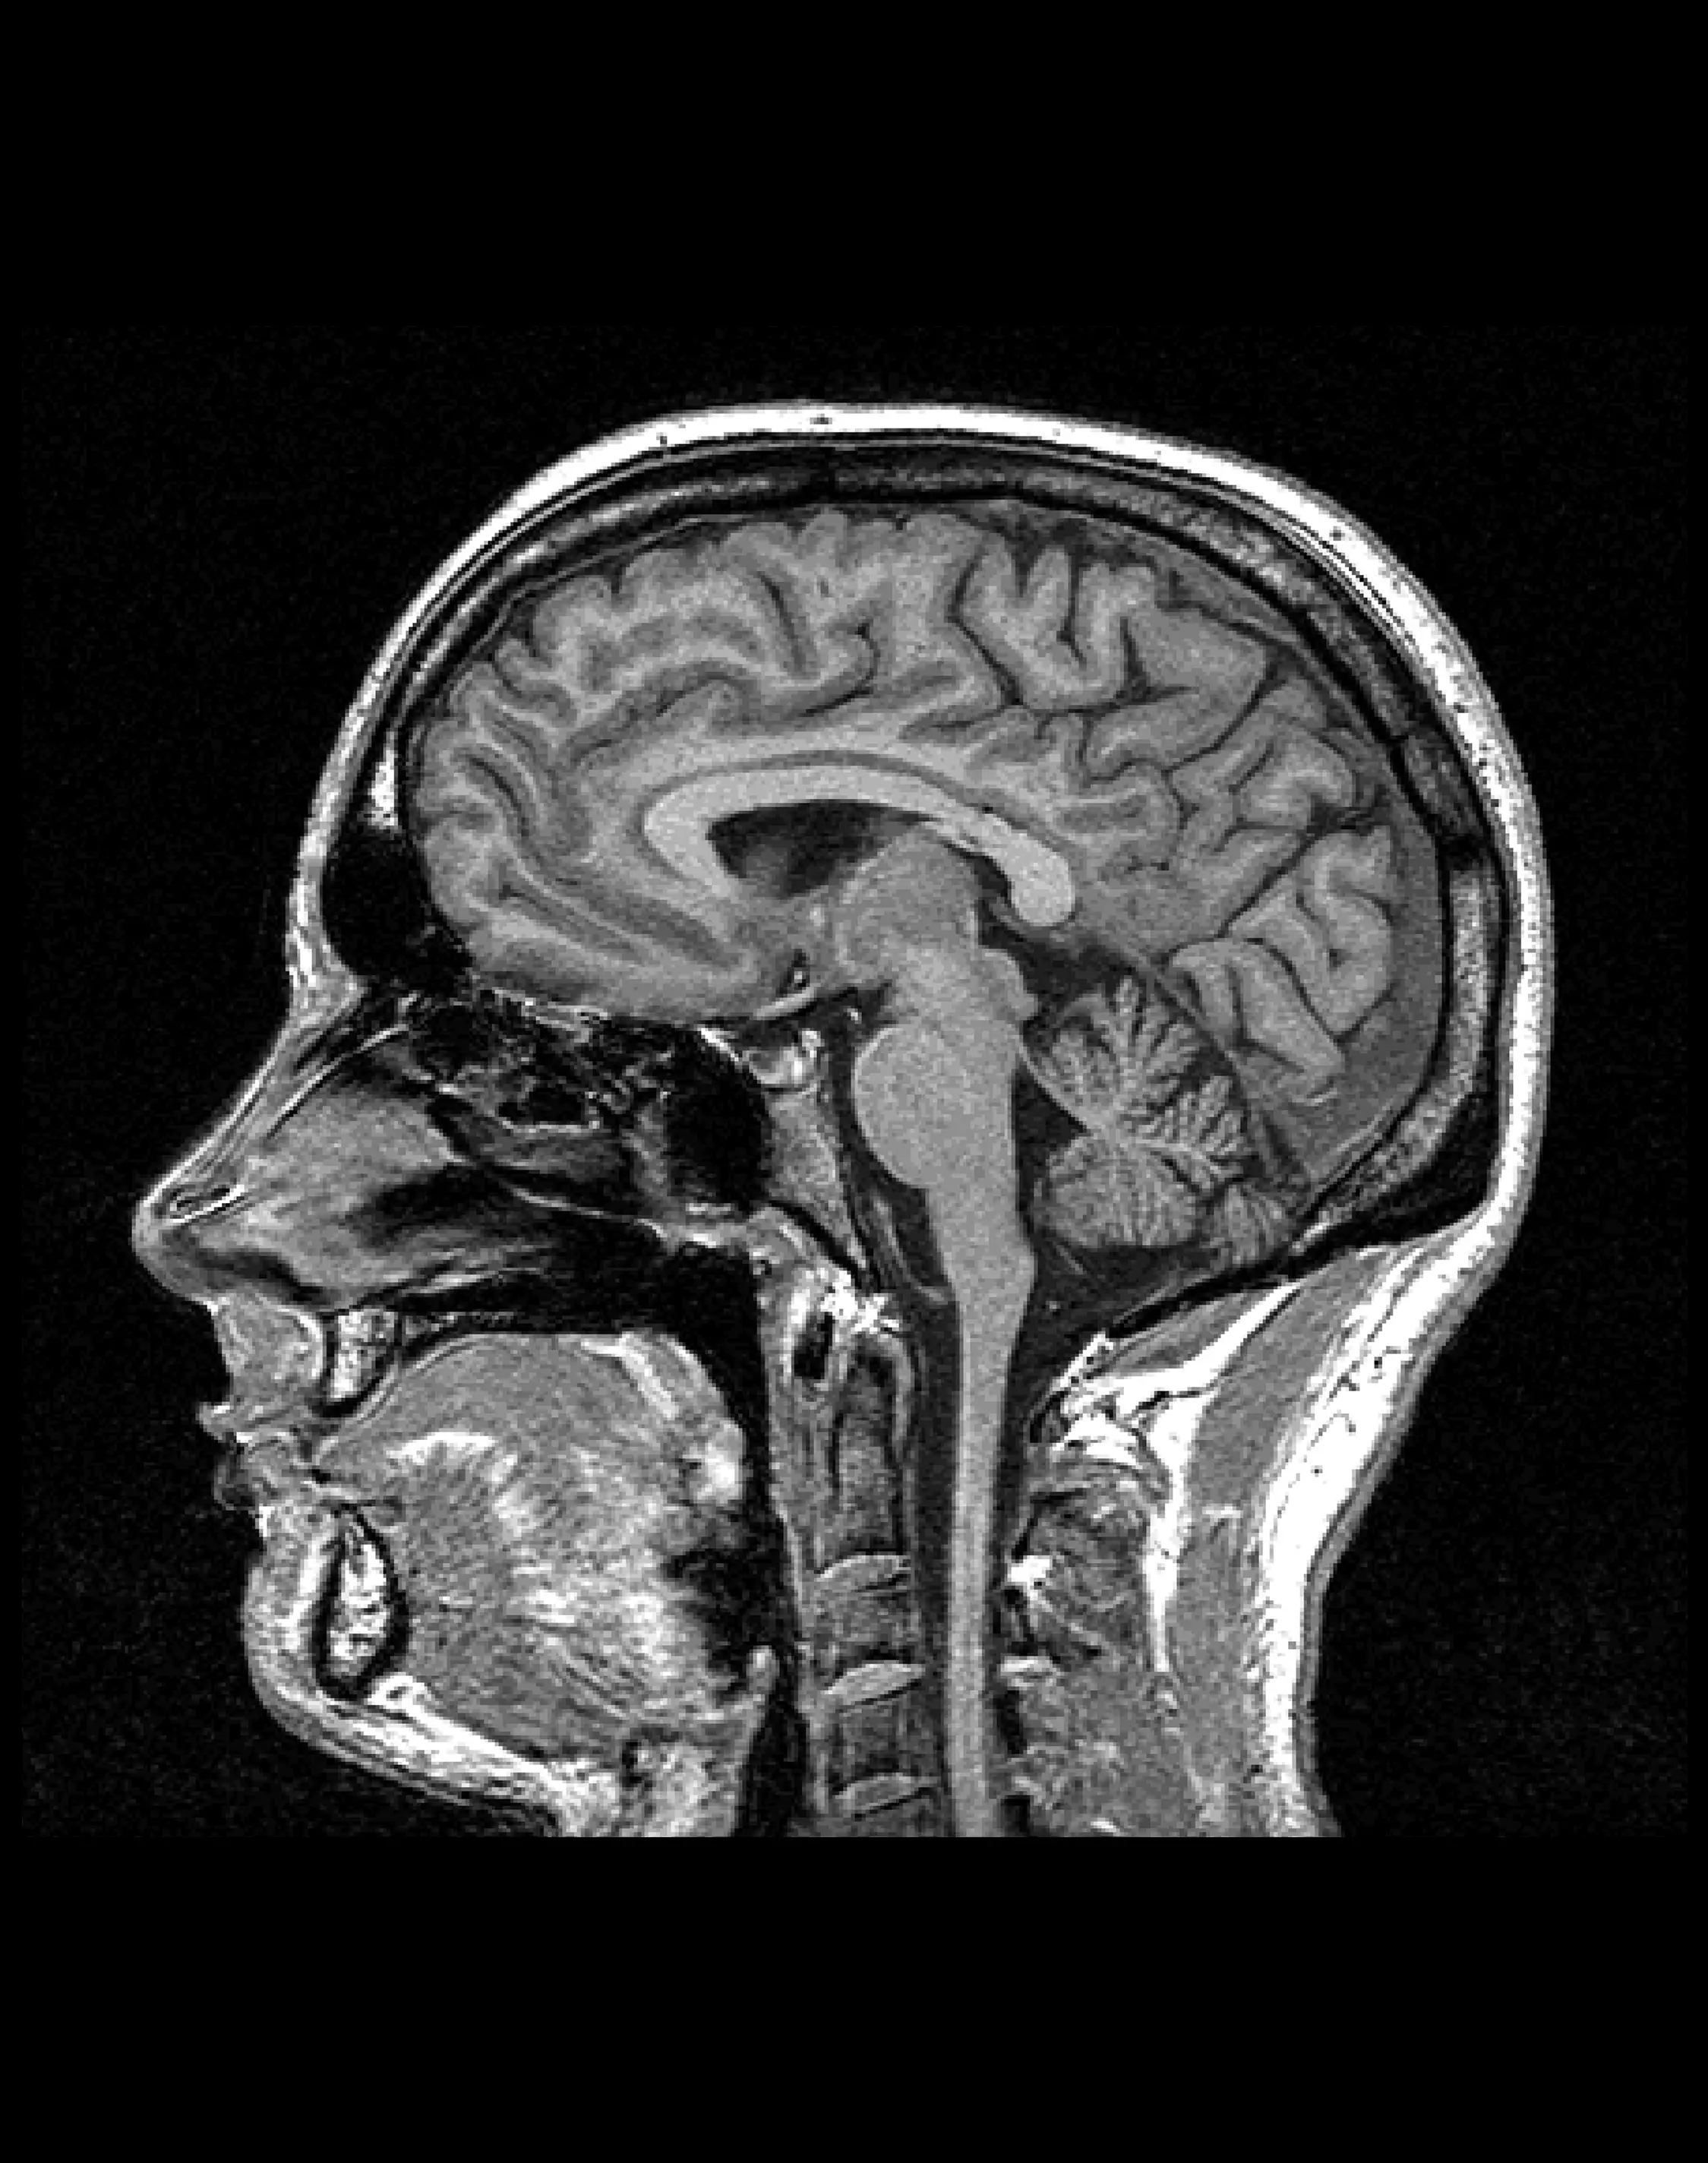

Диагностика состояния артериальных сосудов головного мозга, выявление аневризм, стенозов и других сосудистых аномалий.

Показания:

— Подозрение на сосудистые мальформации, аневризмы

— Выявление анатомических аномалий артерий

— Нарушения мозгового кровообращения

— Подозрение на тромбоз